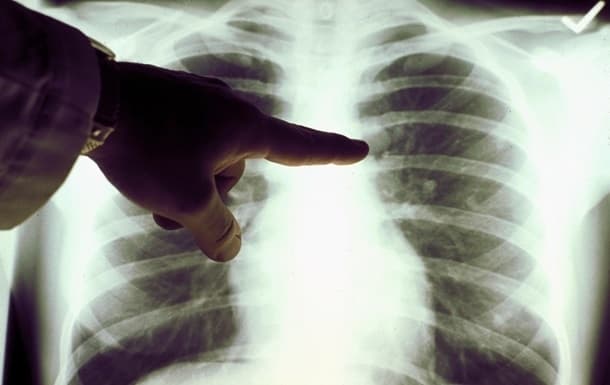

Варто зазначити, що визначити чи у пацієнта справді запалення легень, може тільки лікар. Для встановлення діагнозу використовують рентгенологічне обстеження, прослуховування лікарем легень та обов'язково – лабораторні аналізи.